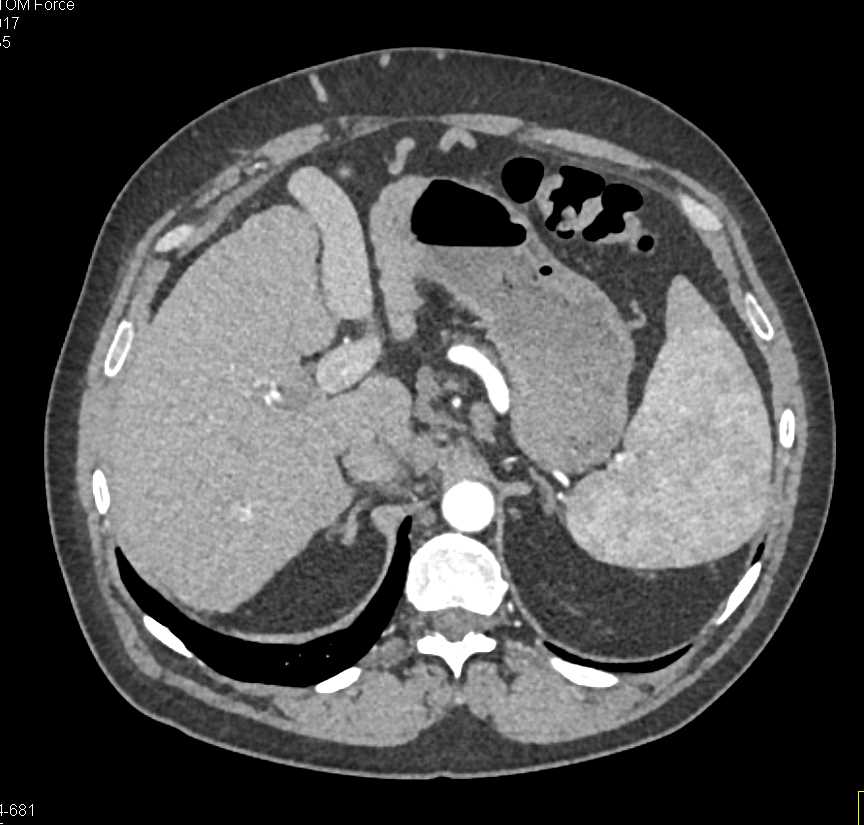

Carcinoma Cecum Obstructs the Small Bowel and Also Liver Metastases